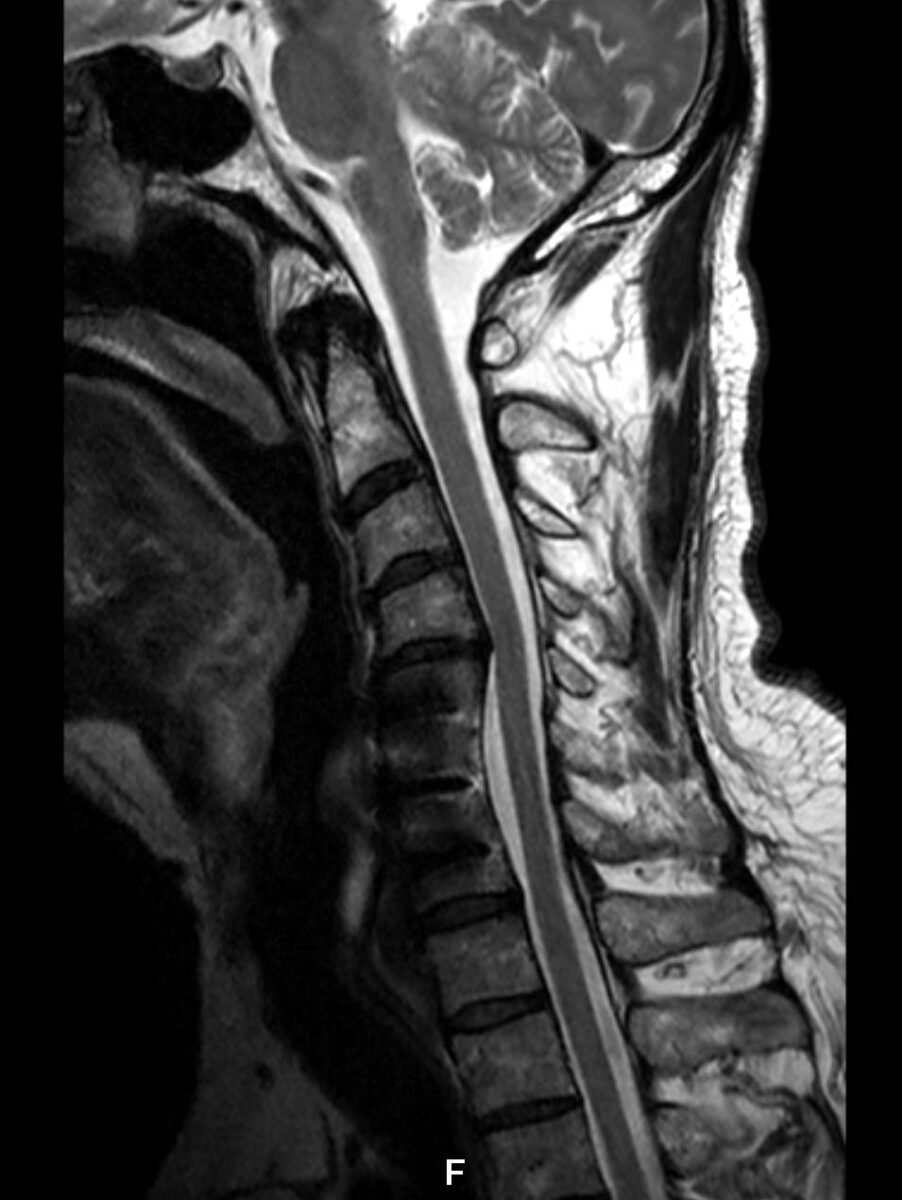

- Imaging studies: MRI of the cervical spine (and CT/X-ray if required) to confirm disc herniation, stenosis, or instability.

- The damaged disc is removed completely

- Pressure on the spinal cord and nerve roots is relieved

- Bone spurs or thickened ligaments may also be removed